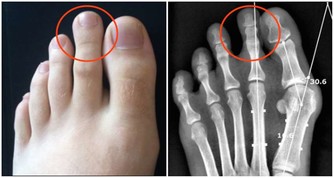

之前我寫過一篇《你覺得錢重要,還是健康重要?》的文章,看到有個朋友留言說,她曾因為晚睡,埋下病根,高考前突然爆發,花掉了家裡兩萬塊錢,住院半個月。進醫院的第一天做了很多檢查,期間還做了手術,直到現在都還需要進行定期檢查。

因為有了這樣的經歷,她告別了凌晨四點,現在基本上都不會超過晚上11點才睡覺了。